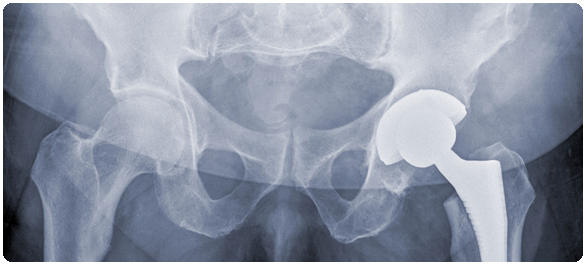

ผศ.นพ.ธนินนิตย์ กล่าวด้วยว่า การรักษาด้วยการผ่าตัดจะช่วยให้ผู้ป่วยสามารถลุกเดิน เคลื่อนไหวได้ไวขึ้น มีการเกิดโรคแทรกซ้อนน้อย และช่วยลดอัตราการเสียชีวิตลงได้ การผ่าตัดส่วนใหญ่นั้นขึ้นอยู่กับตำแหน่งการหักของกระดูกสะโพก บางครั้งก็ใช้วิธีการผ่าตัดยึดตรึงกระดูกด้วยแผ่นเหล็ก บางครั้งก็ผ่าตัดเปลี่ยนข้อสะโพกเทียม

- การเปลี่ยนสะโพกบางส่วน (Partial hip replacement) – กรณีช่วงปลายของกระดูกเคลื่อนหรือถูกทำลาย แพทย์อาจทำการเปลี่ยนกระดูกต้นขาส่วนหัวและส่วนคอด้วยอวัยวะเทียม (Prosthesis) ที่เป็นโลหะ

- การเปลี่ยนสะโพกทั้งหมด (Total hip replacement) – กรณีเคยมีปัญหาเรื่องข้อต่ออักเสบ (Arthritis) หรือบาดเจ็บมาก่อน หรือเป็นโรคกระดูกพรุน ก็อาจทำการเปลี่ยนสะโพกทั้งหมดไปในทีเดียว